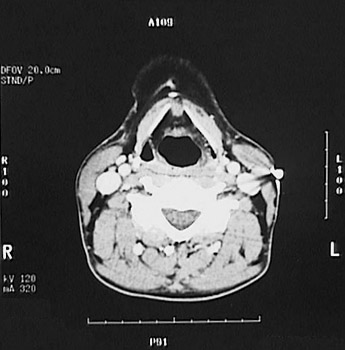

This is a normal axial head and neck CT scan demonstrating the thyroid cartilage and pharynx and C4 and spinal canal and internal jugular vein and internal carotid artery and external carotid artery and trapezius muscle and splenius capitis muscle and sternocleidomastoid muscle.